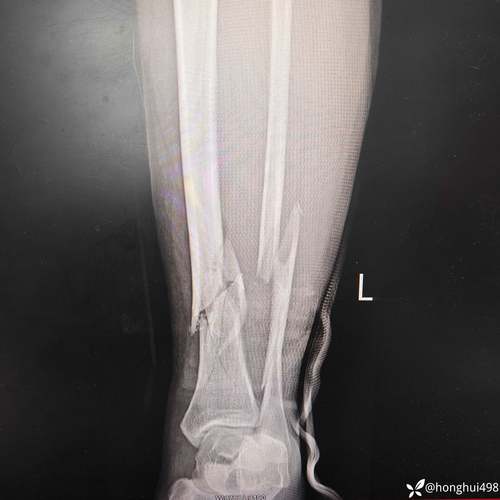

体育资讯3月13日讯 美因茨官方确认,队内27岁前锋西拉斯左胫骨和腓骨骨折。

西拉斯在美因茨对阵奥洛莫茨的欧协联1/8决赛首回合比赛中受伤,美因茨官方发布公告,确认球员左胫骨和腓骨骨折。